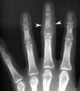

Dactylitis

Lucent defect in bones of hands, wrists, feet, or ankles

Lytic phalangeal lesion